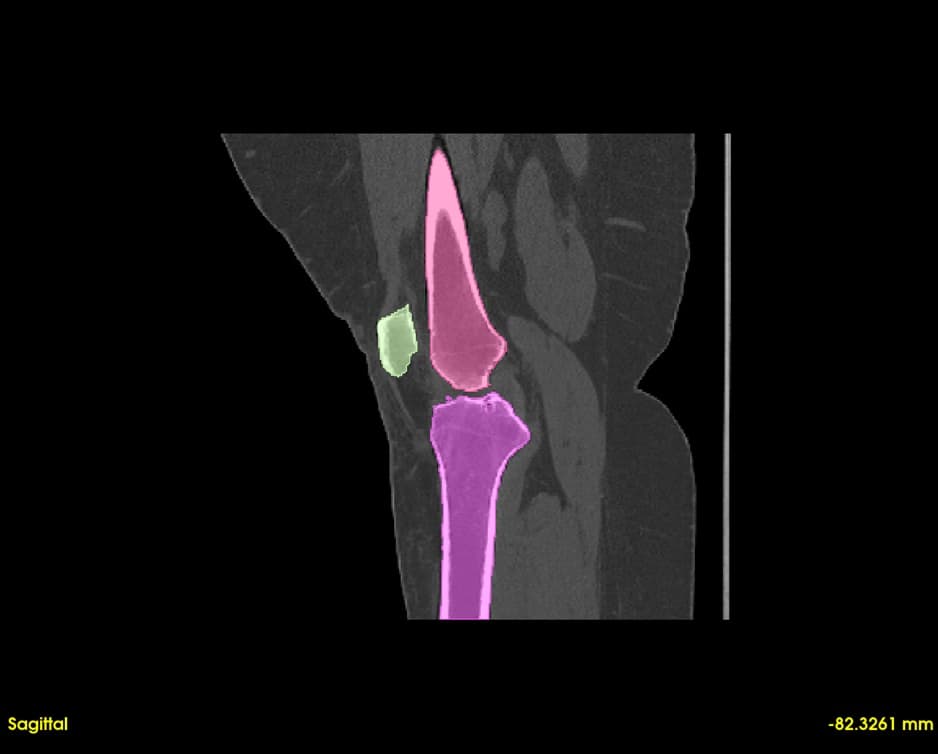

Segment bones, vasculature, and soft tissues with precision. User-friendly tools for accurate anatomical boundary delineation.

Real-time 3D rendering of segmented structures. Create patient-specific anatomical models for visualization and analysis.

Simultaneous axial, sagittal, and coronal views. Navigate through slices with synchronized cross-referencing.